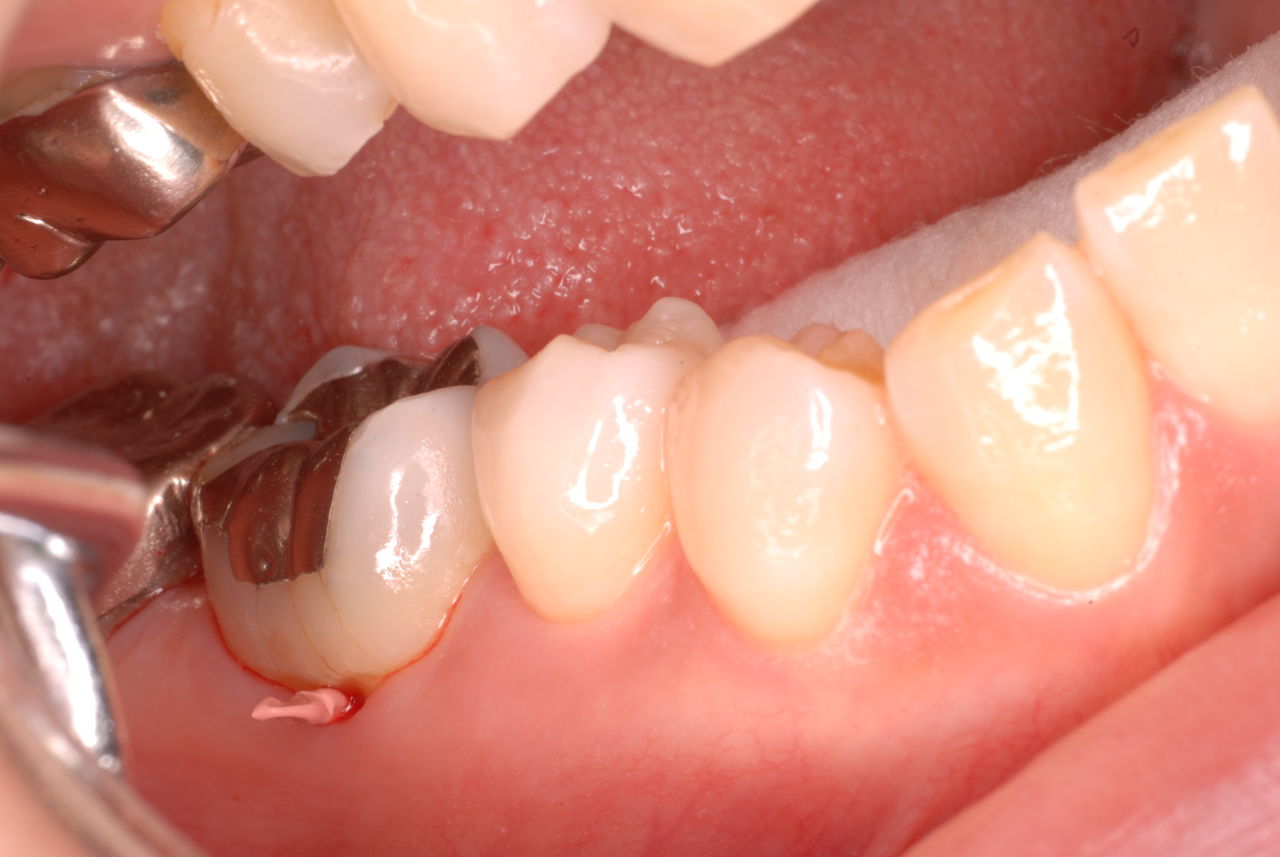

他の都心の矯正歯科で治療中で、ほぼ終了近くの方でした。歯並びで言えば上下の歯が突出していて唇が閉じにくいというのをなんとかしたい。そして歯を抜かないで出来るところを探して都心の矯正歯科への通院となりました。ところが本人曰くよく噛めないというのです。

相談しても“問題無い”の説明だけだそうです。調べたところ歯周病は進行しているし、奥歯の大きい歯2本ずつ計4本はしっかり噛んでいないのです。よく噛めないというのはそのことのようでした。これを矯正的に元に戻すことはできない訳ではありませんが、時間と手間がかかるのは間違いないことです。

歯を削らないといいましても結局歯の間を削りスペースを確保したそうですから、何らかの歯に対する傷害はしているのです。それは虫歯や歯周病を起こしやすい理由にもなりますからこれからも要注意なのです。二年間という貴重な時間を費やしていますから患者本人は大変だったと思います。そして二年間を要したならば更に二年間動かないようにするための入れ歯やマウスピースを装着し続けなければいけないのです。